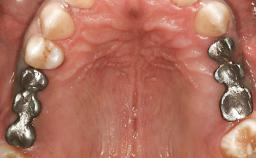

Dr. Gallucci is the Chair of the Department of Restorative and Biomaterial Siences at Harvard School of Dental Medicine. ITI Fellow since 2004, Chair of the ITI Scholarship Center at Harvard.